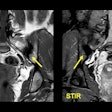

MRI sheds light on axial spondyloarthritis